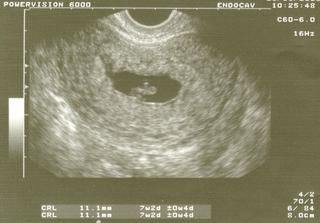

♥ 29.1.2009♥ 1. UTZ - Brouček má 11 mm, jsme 7+2tt a krasně nám bije srdíčko. Tatínek i maminka jsou šťastní a věří v dobrý konec.